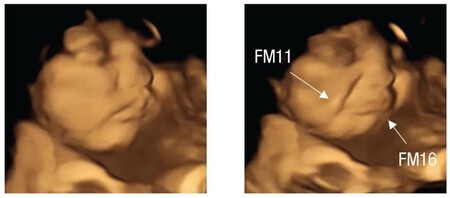

En cambio, cuando los bebés son expuestos al sabor de la col rizada o kale, la mayoría hace un gesto de desagrado. Estira las comisuras de los labios hacia abajo, haciendo un gesto de presión, lo que solemos asociar con cara de disgusto, tristeza o llanto.

Col-rizada-bebe Bebé antes y después de ser expuesto al sabor de la col rizada